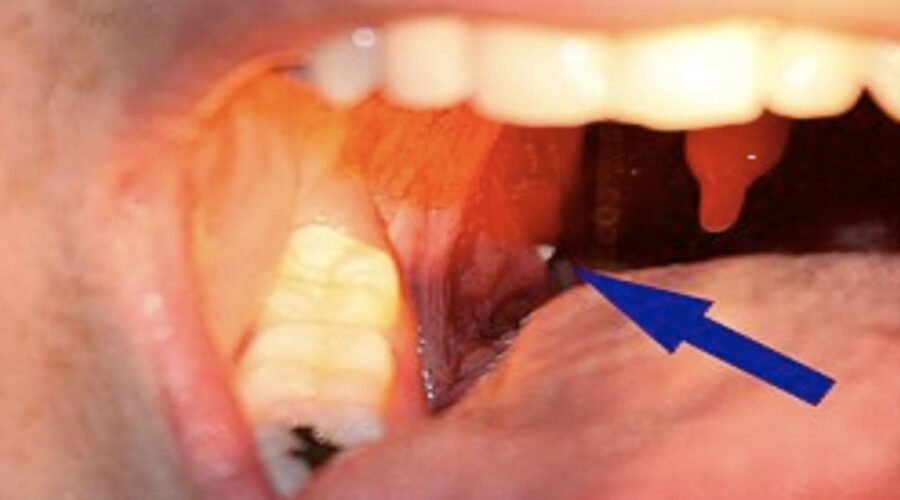

Como já mencionado, os cáseos são pequenas massas sólidas que se formam nas amígdalas. Eles surgem a partir do acúmulo de restos alimentares, células descamadas e outros resíduos orgânicos.

Essas partículas ficam presas nas criptas das amígdalas, e, em contato com o cálcio presente na saliva, acabam endurecendo. O mau cheiro aparece justamente por causa da decomposição desse material.